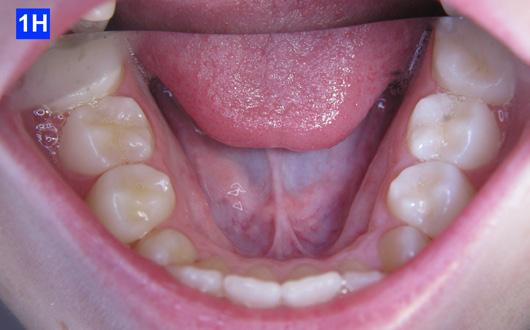

Clinical Micro-esthetic appraisal revealed Angle Class I molar relationship. The arches were narrow, there was crowding, and she had a posterior crossbite. The patient had 2.0 mm overjet and 1.5 mm overbite. There was an anterior cross bite on #12(7) and #22(10), which indicates Class III tendency. The lower airway was very narrow, only 5.0 mm; however, the patient denied SDB symptoms. She did, however, present with symptoms and signs of TMJ dysfunction (Figure 1-D, E, F, G, H,)

Figure 1G: Pre-treatment, maxilla, occlusal view

Figure 1H: Pre-treatment, mandible, occlusal view

Clinical nano-esthetic appraisal revealed no signs of erosion, abfraction, attrition and abrasion. Periodontal health was good, and the patient was devoid of tooth decay. However, there were amalgam restorations on deciduous molars, ready to exfoliate. Maxillary lateral incisors were narrow.